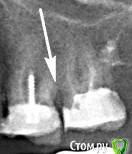

Наталия1966 Опубликовано 3 октября, 2019 Автор Поделиться Опубликовано 3 октября, 2019 Скалывается потому что зуб почти полностью слеплен из пломбы и не выдерживает нагрузку при жевании. А если еще пломба не монолитная а доставлялась частями в разное время то вероятность сколов еще больше.. Надежный вариант в вашем случае - это коронкаДа нет выдерживает очень хорошо 10 лет я не обращалась он отлично стоял, но во второй раз в этом месте прямо по тому же контуру пломба скололась, а так как была очень крепкой, то не вылетела, а скол, раздробившись на кусочки, просел в промежуток между зубами и так еще лет 5 я проходила. Потом мне года полтора высверлили всю подправили сам зуб и очень аккуратно идеально прям на место новую притерла врач и через некоторое время опять по тому же контуру скол, раздробление и проседание в промежуток между зубами. Вот что это я не знаю, На снимке там какой то кусок стенки выше контура основной пломбы, черт его знает. Записалась еще пойду... Ссылка на комментарий

Наталия1966 Опубликовано 12 ноября, 2019 Автор Поделиться Опубликовано 12 ноября, 2019 это как платье,все в заплатках,уже родной ткани не осталось,одни разноцветные лоскутки.А его опять принесли к портному с просьбой залатать очередную прорехукорень отличный, не надо садистски усугублять ситуацию - залатать прореху. Да иногда и залатать, а не дергать. Хороший, отличный, залитый корень, но на контакте с другим зубом идет постоянных скол по одному и тому же контуру, как под копирку сформированной пломбы. Была у доктора, она решила проблему объединив стенки двух зубов общей пломбой. Теперь не отлетит. Просила прижечь сосочек, мож он заваливается и как то мешает, она отказалась, сказав что прижиганье сосочка деформирует немного десну и зачем это надо. И пока стоит не "колышется" 1 Ссылка на комментарий